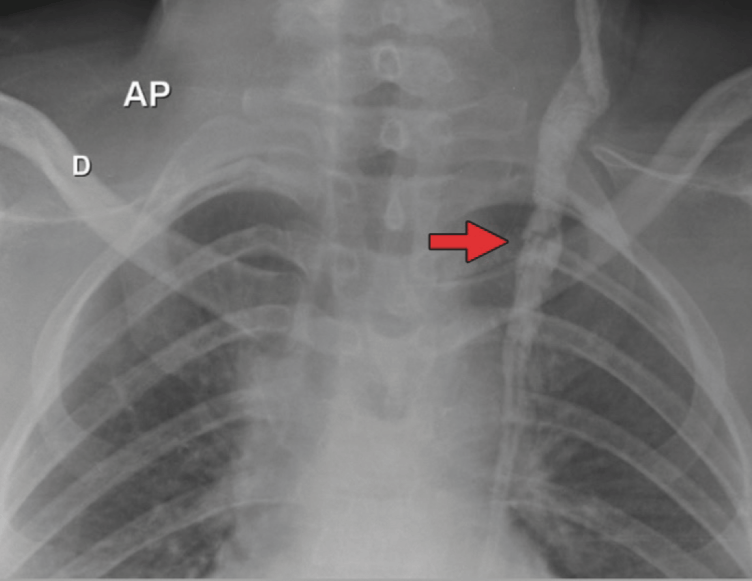

Hydrocephalus is a disorder characterized by the excessive accumulation of cerebrospinal fluid (CSF) in the brain’s ventricles and/or suba- rachnoid spaces, leading to ventricular dilation and increased intracranial pressure (ICP) (1). Ventriculoperitoneal (VP) shunts have long been the standard treatment for hydrocephalus (2). Immediate evaluation for potential shunt malfunction should be performed in patients who develop new or aggravated signs of incre- ased ICP, such as headache, vomiting, lethargy, papilledema, and irritability (3, 4).

Case Report: A 43-year-old female patient, with a history of VP shunt placement since childhood due to obstructive hydrocephalus, presented with headache, blurred vision, vomiting, and papil- ledema. The chest X-ray revealed a fracture of the VP catheter between the second and third left rib arches. The patient underwent a new VP shunt placement on the right side, with immediate improvement in ICP symptoms and reduction of thoracic bulging.